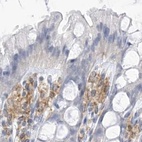

Immunohistochemistry analysis in human spleen and skin tissues using Anti-TBXAS1 antibody. Corresponding TBXAS1 RNA-seq data are presented for the same tissues.